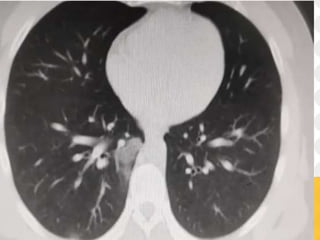

SATURACION DE OXIEGNO DE 90%, SE REALIZA NUEVA TAC SIMPLE

DE TORAX

LABS Y TAC SIMPLE DE TÓRAX

Cambios imagenológicos:

TAC SIMPLE DE TÓRAX:

• 90% sensibilidad, 96% especificidad

• Opacidades en vidrio deslustrado con o sin consolidación

• Engrosamiento pleural

• Compromiso pulmonar bilateral